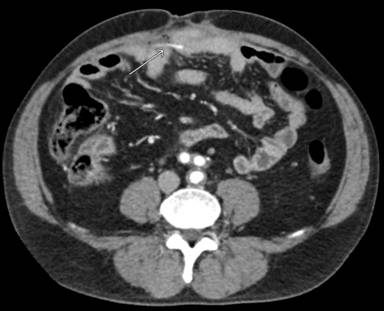

An abdominal CT scan was then performed, confirming the presence of tubular stent in the mesogastrium/right lower quadrant (Figure 1). The tube was strongly attached to small bowel loops that nearby seemed to have thickened walls. It was impossible to establish whether the tube was still intra-luminal or had migrated into the peritoneal cavity. No relevant free-fluid was detected in the abdomen.

Figure 1. After migration, stent perforated small bowel into the peritoneal cavity. (CT scan). |

As seen in this case report, a migrated stent can lead to bowel perforation. The onset can be slow and unclear if perforation does not happen suddenly. Therefore, peritonitis may be localized because of bowel adhesions that surround the perforated bowel loop. CT scan proved to be the best imaging tool to detect perforation and to describe the intra-abdominal position of the stent.